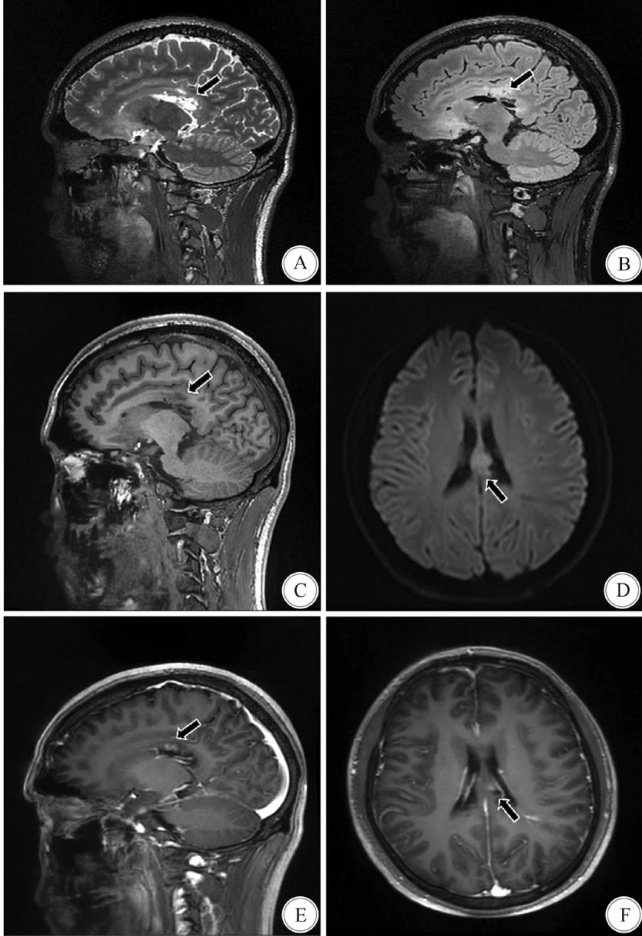

Abstract:ObjectiveTo explore the clinical conditions and imaging results of cerebraland cerebelar atrophy occurredafterchemoradiotherapyforintracranialgerm celltumors,toenhanceunderstandingoflong-term complications asociated with the treatment of intracranial germ cell tumors.MethodsTheclinical dataof a 22- year-old patient withaintracranial germcelltumorinthecorpuscalosumwhowasadmitted totheDepartmentof Neurosurgery.theAfiliated HospitalofSichuanNorth MedicalColegeinJuly2O22wereanalyzedretrospectively. The relevant literature was reviewed.ResultsFollow-up imaging revealed progresiveatrophy of the patient's cerebrumand cerebelum,whichcorrelated with ataxia,cognitive impairment,and motor coordination deficits.The International Cooperative Ataxia Rating Scale(ICARS)score decreased from 76 to 69.ConclusionsThepotential severe neurotoxicityassociatedwith chemoradiotherapy for intracranial germ celltumors,underscoring theneed for enhanced treatment monitoring and individualized strategies to mitigate long-term risks.The underlying mechanisms of disease progression and optimal treatment approaches remain unclear,warranting further research to improve therapeutic efficacy and prognosis.